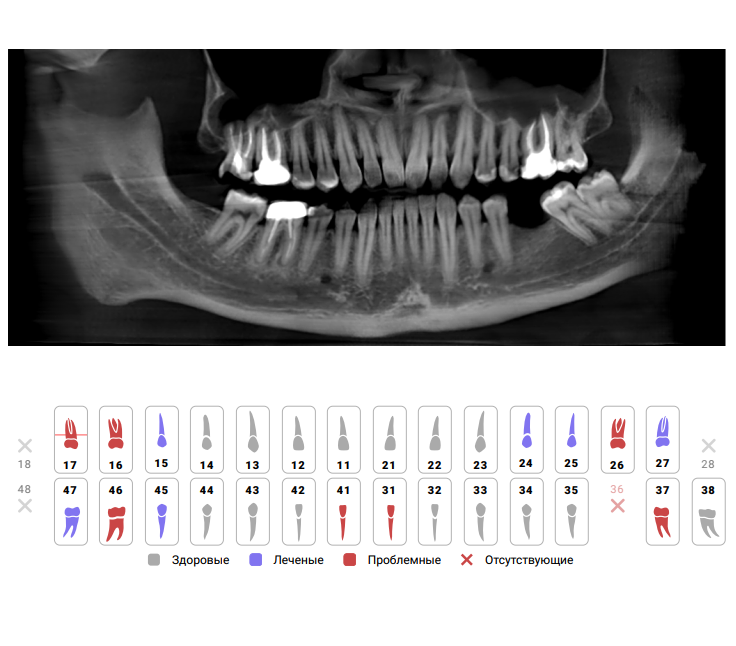

Давайте рассмотрим конкретный пример того, как ИИ может использоваться для прогнозирования подвижности зубов. Представьте себе, что пациент приходит на прием к стоматологу. Врач делает рентгеновский снимок и загружает его в систему, оснащенную ИИ.

ИИ анализирует снимок и выявляет признаки, которые могут указывать на повышенный риск подвижности зубов, такие как:

- Уменьшение плотности костной ткани вокруг зуба

- Изменение формы альвеолярного отростка

- Наличие воспалительных процессов в десне

Затем ИИ учитывает другие факторы риска, такие как возраст пациента, его медицинская история и образ жизни. На основе этих данных система выдает прогноз, указывающий на вероятность развития подвижности зубов в течение определенного периода времени (например, через год, два или пять лет).